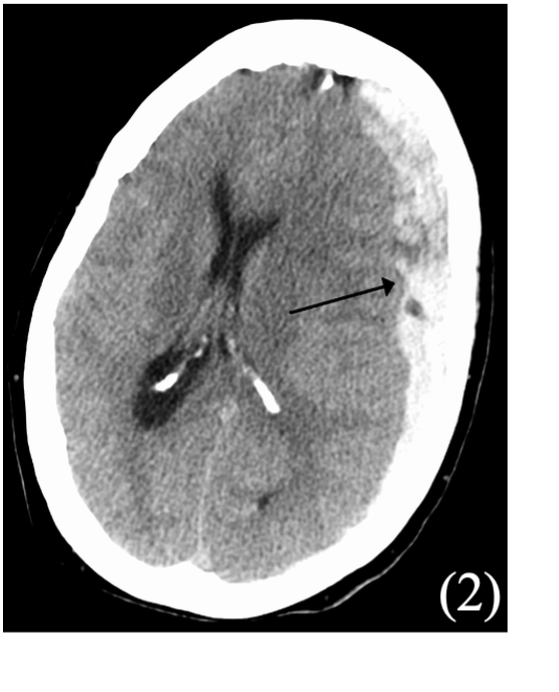

Subdural Haematoma

This is a collection of blood between the dura and arachnoid mater of the brain.

It is categorised as acute (< 3 days, associated with high impact trauma), subacute (3–21 days), or chronic (> 21 days, more common in elderly and alcoholics).

Can be due to high impact trauma to head, rupturing the bridging veins in the dural venous sinuses, but also secondary to metastases and rupture of aneurysms.

Non-contrast CT shows concave “banana” shape (does cross suture lines)